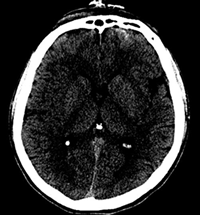

急性水頭症の具体例

急性水頭症では、脳室が拡大して頭蓋骨の内側の圧力が高まり、激しい頭痛、嘔吐、意識障害などが生じます。

さらに、脳室の拡大による圧迫が脳ヘルニアの状態まで進行すると、深部にある脳幹が侵されて呼吸障害などを生じ、最悪の場合には死に至ります。

急性水頭症に対しては、脳室ドレナージ術を緊急で行います。局所麻酔をかけて頭蓋骨に小さな孔をあけ、脳室にチューブを挿入します。脳脊髄液とともに、脳室内の出血を取り除きます。

画像の中央部に白く細長い像がありますが、これは、脳室内出血を抜き取るためのドレインチューブが映ったものです。